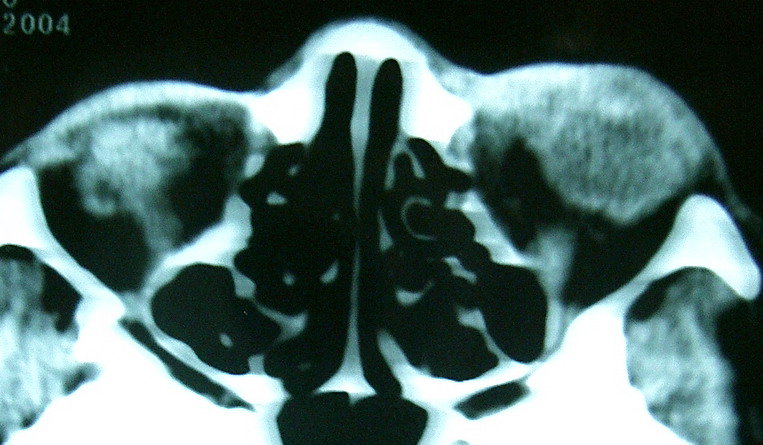

2,上眼眶CT示:左眼眶内肿物

此主题相关图片如下:

按此在新窗口浏览图片

眼眶冠扫,平扫CT:

左眼球内上方可见不规则软组织块影,大小约2.5*1.0CM,与邻近组织分界不清,相邻之内直肌、上直肌增粗,眼环正常,眶壁骨质无破坏,左上颌窦底部可见粘膜增厚,其余副鼻窦未见异常。

IMP:1,左眼眶肿物;2,左上颌窦炎